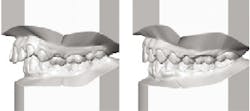

The objective of this paper is to stress the significance of making and retaining conventional diagnostic stone casts of a patient's mandible, maxilla, teeth, and the surrounding tissues. Full-arch diagnostic casts are valuable tools in determining various physiological and morphological changes that take place during the life span of the jaws, teeth, and periodontal tissues (Figs. 1-5).

Digital imaging impressions can also be used to make extremely accurate stone casts, which reproduce the jaws, teeth, gingival tissues, and palatal area (Fig. 6).1-4 Though the intraoral digital scanners are moving rapidly into the profession, use of conventional materials remain the most common source for making impressions. Stone casts are familiar to practitioners and, at this time, provide precise information on the bone, tissues surrounding the teeth, as well as their morphology and position. Use of stone casts can be an effective means of patient education, as they provide comparable observation of the changes that have taken place over time in the position and anatomy of teeth, bone, and soft tissues. A few noteworthy examples are demonstrated in Figs. 1-5.

Occlusion constantly changes, and comparison of the changes on stone casts provide valuable information to the practitioner and can be used to educate the patient.5

k. Retaining casts for future reference to monitor any changes in occlusion